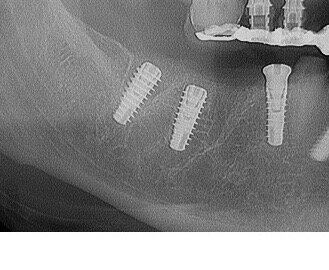

Fig. 14 - Controllo rx Post-chirurgico time 0: Si valuta bene la posizione intra-alveolare degli Impianti Multysytem.

Fig. 15 - Controllo rx a 120 gg. Gli impianti sono integrati nella nuova sede formatasi.